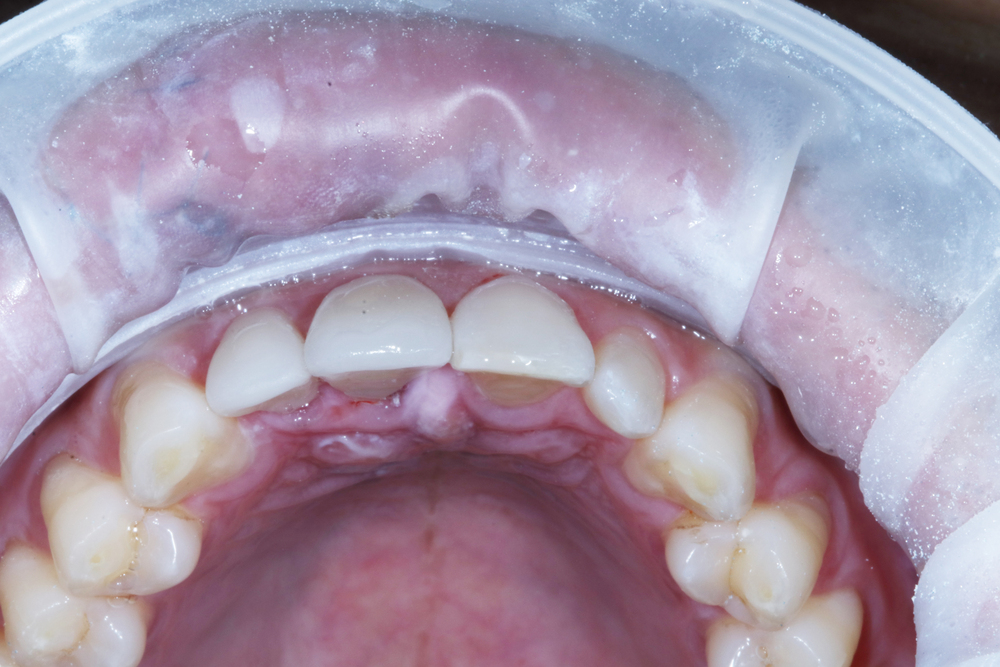

위에서 본 모습입니다. 이렇게 사고 당일에 치료가 완료되었어요. 입천정쪽으로 보시면 사고 당일이라는 것이 보이네요. 앞쪽에서는 거의 티가 안났지만 말이죠. 이렇게 치료가 끝났어요. 하지만 위에 설명글을 올려드린대로 부러진 정도에 따라서 치료는 다르게 진행되기도 해요. 12번 측절치는 결국 몇년 후에 발치하고 임플란트로 바꾸게 되긴 했지만 그래도 처음 치료가 이렇게 이루어진 부분에서는 좋은 결정이었던 거 같아요.